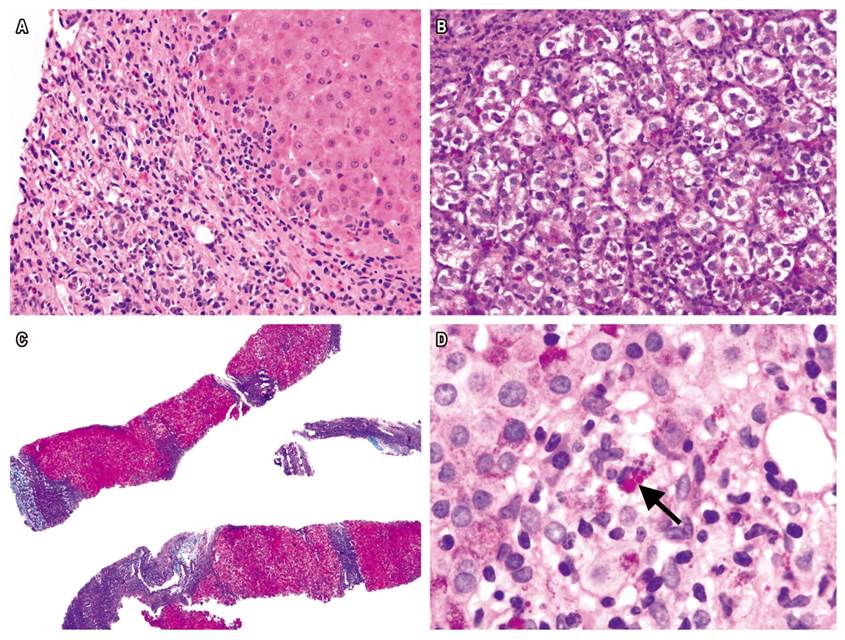

Liver biopsy samples were taken from 85.7% of the patients at the beginning of the disease (Figure 1). Reevaluation of biopsies confirmed the diagnosis of AIH based on the presence of interface hepatitis (77.8%), lymphoplasmacytic infiltrate in portal spaces (94.4%) and rosette formation in liver cells (50.0%). It should be noted that the liver biopsies of 6 of 18 children (33.3%) showed cirrhosis. As of this writing, despite treatment with corticosteroids and azathioprine, four patients have undergone liver transplantation and two are on the waiting list. The presence of hyaline droplets in the cytoplasm of Kupffer cells was verified in 42.9% of cases.

Figure 1 A. H&E stain of liver biopsy from AIH patient shows interface hepatitis and portal lymphoplasmacytic infiltrate (400x). B. Rosette formation (400x). C. Masson’s trichrome shows regenerative nodules surrounded by fibrotic septa (40x). D. PAS-diastase stain shows hyaline drops in Kupffer cells (1000x).

Several studies indicate that the simplified criteria have excellent sensitivity and specificity for pediatric patients except those cases with fulminant liver failure. 25 A novel histological finding recently described by Tucker et al. is the presence of hyaline drops in the cytoplasm of Kupffer cells. This provides information that distinguishes AIH from other forms of chronic hepatitis. 12 In our cases, the most frequent histopathological findings were portal lymphoplasmacytic infiltrate and interface hepatitis. Hyaline drops were present in 42.9% of the liver biopsies.